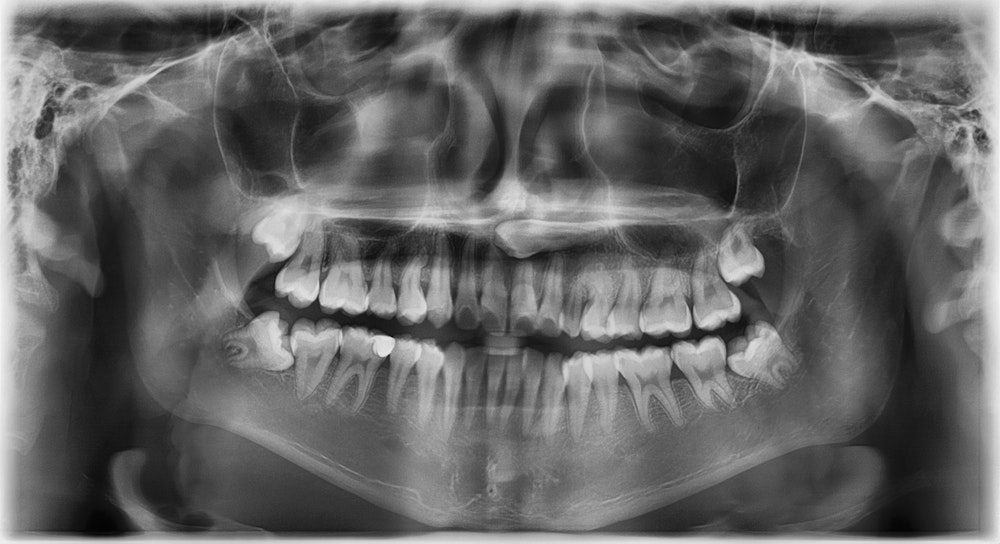

You should have your wisdom teeth examined even if you are not experiencing any pain or dental issues. Our experienced dentists can review your X-rays to determine the growth pattern of your wisdom teeth to ensure they will not affect your oral health.

Our Fairfax dental practice uses the latest state-of-the-art technology available in dentistry. We use the world's most advanced X-ray machine so we can have a clear picture of how your wisdom teeth are growing. We can suggest and perform the best possible treatment with the help of our advanced technology.